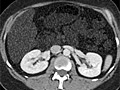

A computed tomography (CT) scan uses X-rays to make detailed pictures of structures inside of the body.

During the test, you will lie on a table that is attached to the CT scanner, which is a large doughnut-shaped machine. The CT scanner sends X-rays through the body area being studied. Each rotation of the scanner provides a picture of a thin slice of the organ or area. All of the pictures are saved as a group on a computer.

A CT scan can be used to study all parts of your body, such as the chest, belly, pelvis, or an arm or leg. It can take pictures of body organs, such as the liver, pancreas, intestines, kidneys, bladder, adrenal glands, lungs, and heart. It also can study blood vessels, bones, and the spinal cord.